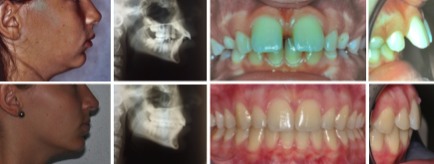

Fall 2: Offener Biss und Engstände

Therapie: Vollfixe Spange und Chirurgie